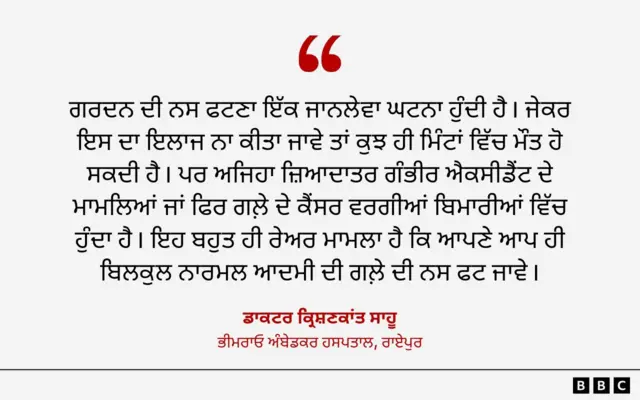

ਇਸੇ ਵਿਭਾਗ ਦੇ ਐਚਓਡੀ ਡਾਕਟਰ ਕ੍ਰਿਸ਼ਣਕਾਂਤ ਸਾਹੂ ਨੇ ਬੀਬੀਸੀ ਨਿਊਜ਼ ਹਿੰਦੀ ਨਾਲ ਗੱਲ ਕਰਦਿਆਂ ਕਿਹਾ, "ਗਰਦਨ ਦੀ ਨਸ ਫਟਣਾ ਇੱਕ ਜਾਨਲੇਵਾ ਘਟਨਾ ਹੁੰਦੀ ਹੈ। ਜੇਕਰ ਇਸ ਦਾ ਇਲਾਜ ਨਾ ਕੀਤਾ ਜਾਵੇ ਤਾਂ ਕੁਝ ਹੀ ਮਿੰਟਾਂ ਵਿੱਚ ਮੌਤ ਹੋ ਸਕਦੀ ਹੈ। ਪਰ ਅਜਿਹਾ ਜ਼ਿਆਦਾਤਰ ਗੰਭੀਰ ਐਕਸੀਡੈਂਟ ਦੇ ਮਾਮਲਿਆਂ ਜਾਂ ਫਿਰ ਗਲ਼ੇ ਦੇ ਕੈਂਸਰ ਵਰਗੀਆਂ ਬਿਮਾਰੀਆਂ ਵਿੱਚ ਹੁੰਦਾ ਹੈ। ਇਹ ਬਹੁਤ ਹੀ ਰੇਅਰ ਮਾਮਲਾ ਹੈ ਕਿ ਆਪਣੇ ਆਪ ਹੀ ਬਿਲਕੁਲ ਨਾਰਮਲ ਆਦਮੀ ਦੀ ਗਲ਼ੇ ਦੀ ਨਸ ਫਟ ਜਾਵੇ।"

ਉਨ੍ਹਾਂ ਅੱਗੇ ਦੱਸਿਆ, "ਇਹ ਇੰਨਾ ਰੇਅਰ ਹੈ ਕਿ ਮੈਡੀਕਲ ਜਰਨਲਜ਼ ਦੇ ਅਨੁਸਾਰ ਦੁਨੀਆ ਭਰ ਵਿੱਚ ਹੁਣ ਤੱਕ ਇਸ ਤਰ੍ਹਾਂ ਦੇ ਕੇਵਲ 10 ਕੇਸ ਹੀ ਦਰਜ ਹਨ।"